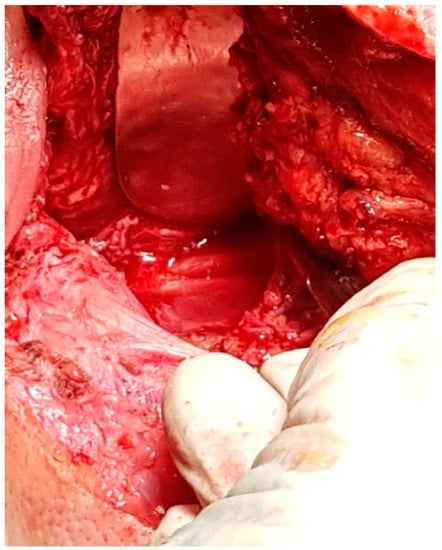

6. Differential Diagnosis of the Extracranial FNS

7. Therapeutic Strategies in the Management of FNS Extracranial Segment